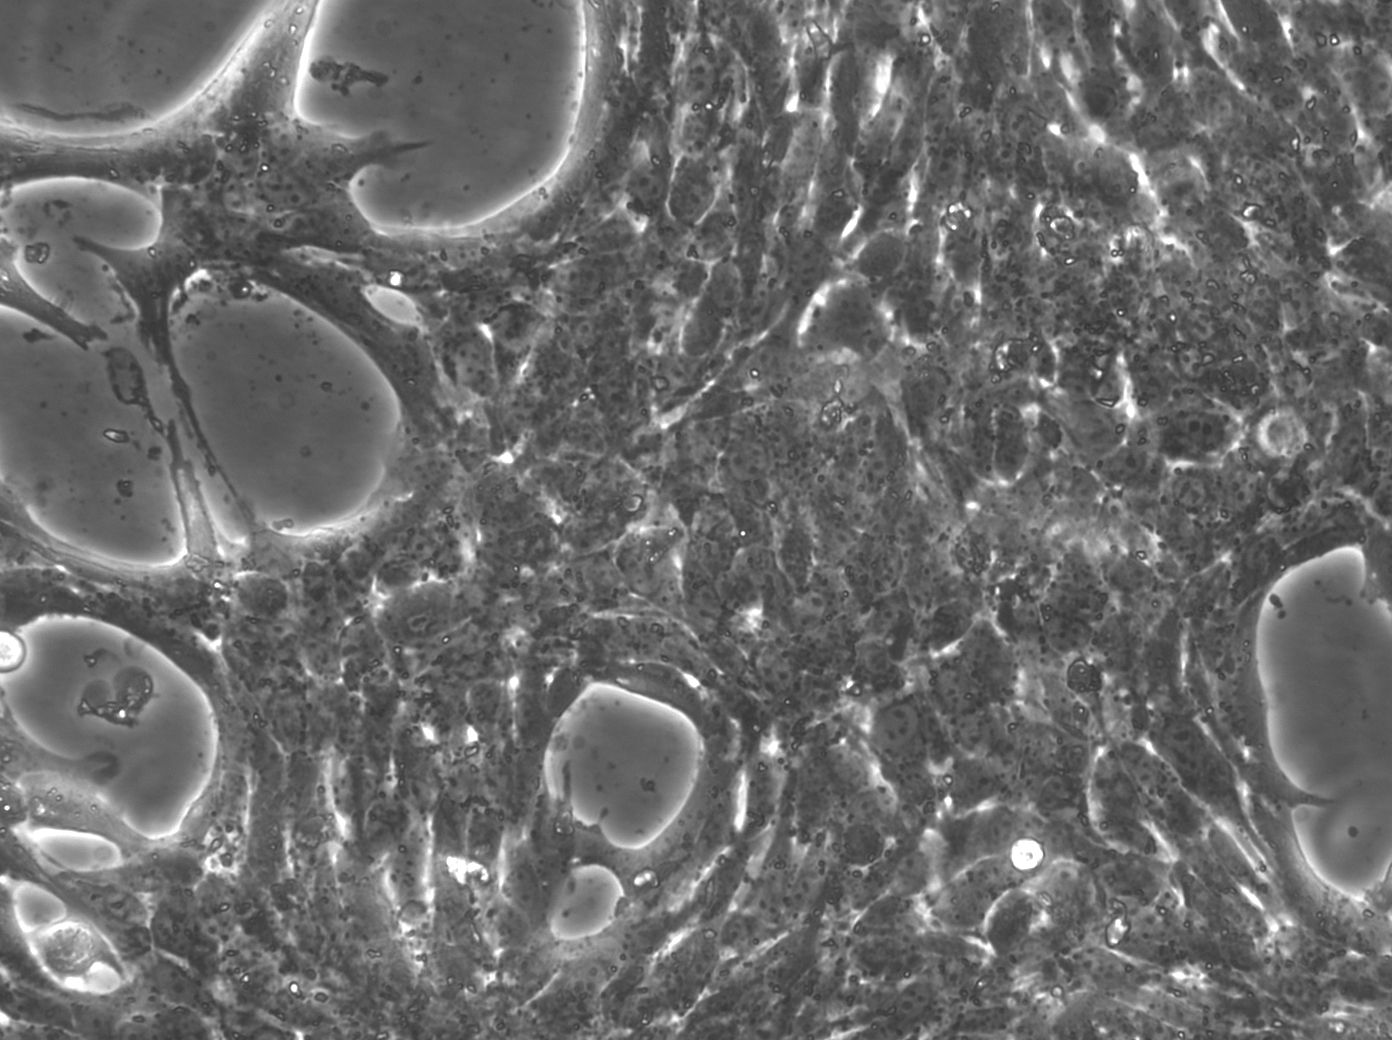

上皮样细胞,贴壁生长 |

来源于 C57BL/6J小鼠的原发性肝细胞癌,这些小鼠肝细胞忠实地代表了肝细胞癌,并为研究这种类型的肝癌提供了有价值的模型,同义词HEP-53.4和53.4,它们便于识别和交叉引用,肝细胞癌是一个重大的健康问题,这些细胞能够对其分子通路、细胞相互作用和治疗策略进行精确研究,这些细胞起源于Mus musculus(小鼠),为理解和开发肝细胞癌的治疗方法提供了相关的模型系统。 |